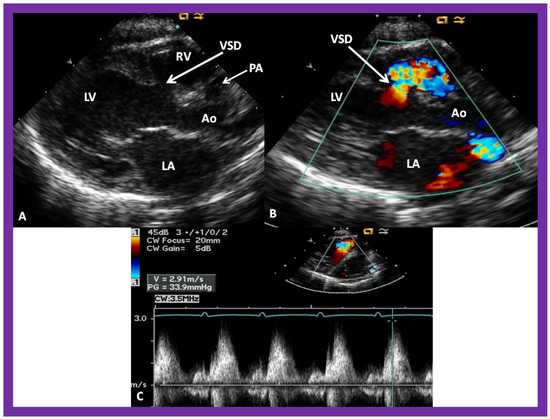

Figure 10. Selected video frames from parasternal long axis views of a patient with tricuspid atresia with normally related great arteries demonstrating an enlarged left atrium (LA) and left ventricle (LV), a small right ventricle (RV) and a moderate sized defect (VSD) (thick arrow) on 2D (A) and color flow (B) imaging. The turbulent flow (B), with a Doppler flow velocity of 2.91 m/s by continuous wave Doppler (C) across the VSD, suggests some restriction of the VSD. Ao, Aorta; PA, pulmonary artery. Reproduced from Reference [29].

Then, the ventricular septum is evaluated; the ventricular septum is intact in most Type Ia cases. In children with Type I (normally related great arteries), the VSD supplies the pulmonary blood flow (Figure 10) while in patients with Type II (transposition of the great arteries) the VSD allows the blood to flow into the systemic circuit (Figure 11; Figure 12). In Type I patients, the VSD is demonstrated by 2D (Figure 10A), and the left to right shunt across it by color (Figure 10B), pulsed and CW (Figure 10C) Doppler signals. The interrogation of the RV outflow tract and PA region should be performed; recording the peak Doppler flow velocity across the RV outflow tract and the pulmonary valve is helpful in identifying obstruction across these sites. The Doppler data from the VSD and RV outflow tract are also helpful in the estimating of PA pressures. In Type I babies, the 2D size of the VSD and the peak Doppler flow velocity across it are useful in quantifying the size of the VSD (Figure 10). The higher the VSD Doppler flow velocity, the smaller the defect. However, in patients with pulmonary hypertension or severe infundibular or valvar pulmonary stenosis, the VSD Doppler velocities are not reflective of the size of the VSD. Barring these exceptions, RV and PA systolic pressure may be estimated using a modified Bernoulli equation (RV/PA systolic pressure = systolic blood pressure – 4V2).